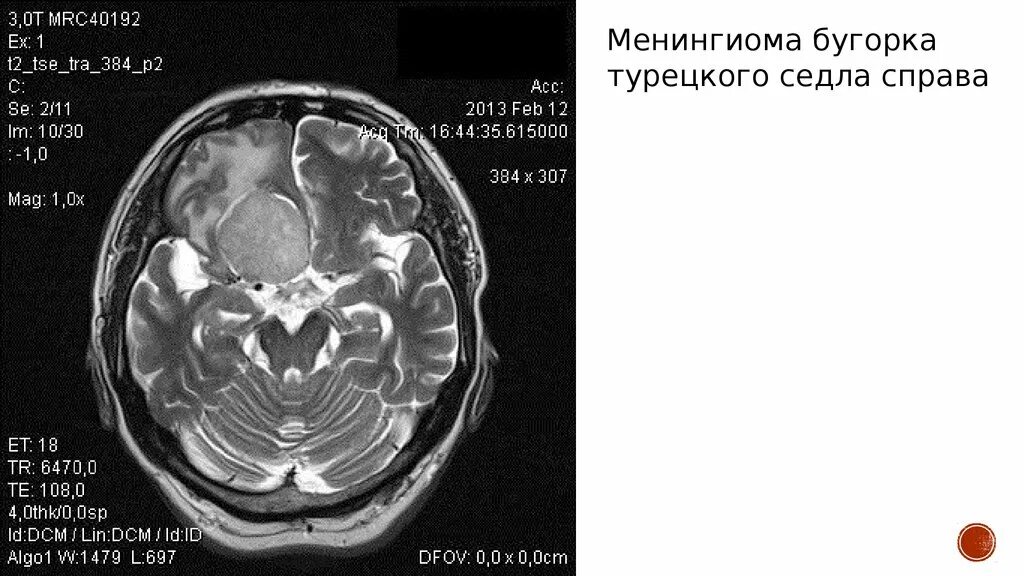

Менингиомы головного мозга мкб